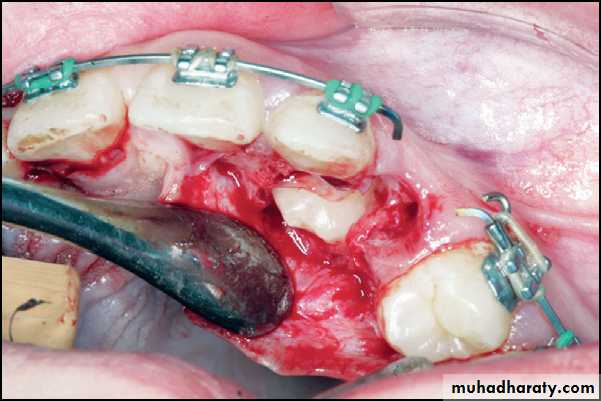

After exposure of the impacted tooth, the overlying bone is removed with a bur or curette, and the follicle is minimally debrided to allow access to the tooth. In the closed technique, the eruption bracket/chain is bonded to the tooth at the time of surgery; in the open technique, it can be done at the time of surgery by the surgeon or done at a subsequent appointment with the orthodontist.

Hemostasis can be achieved using electrosurgery or by packing cotton pellets soaked in hemostatic agents around the exposed tooth. The isolated tooth is then etched, rinsed and dried, and the eruption device bonded to the tooth using a light-cured, acid-etch composite material. Positioning of the bracket as near to or on the incisal edge of the tooth provides the orthodontist with the best mechanical advantage for positioning of the tooth